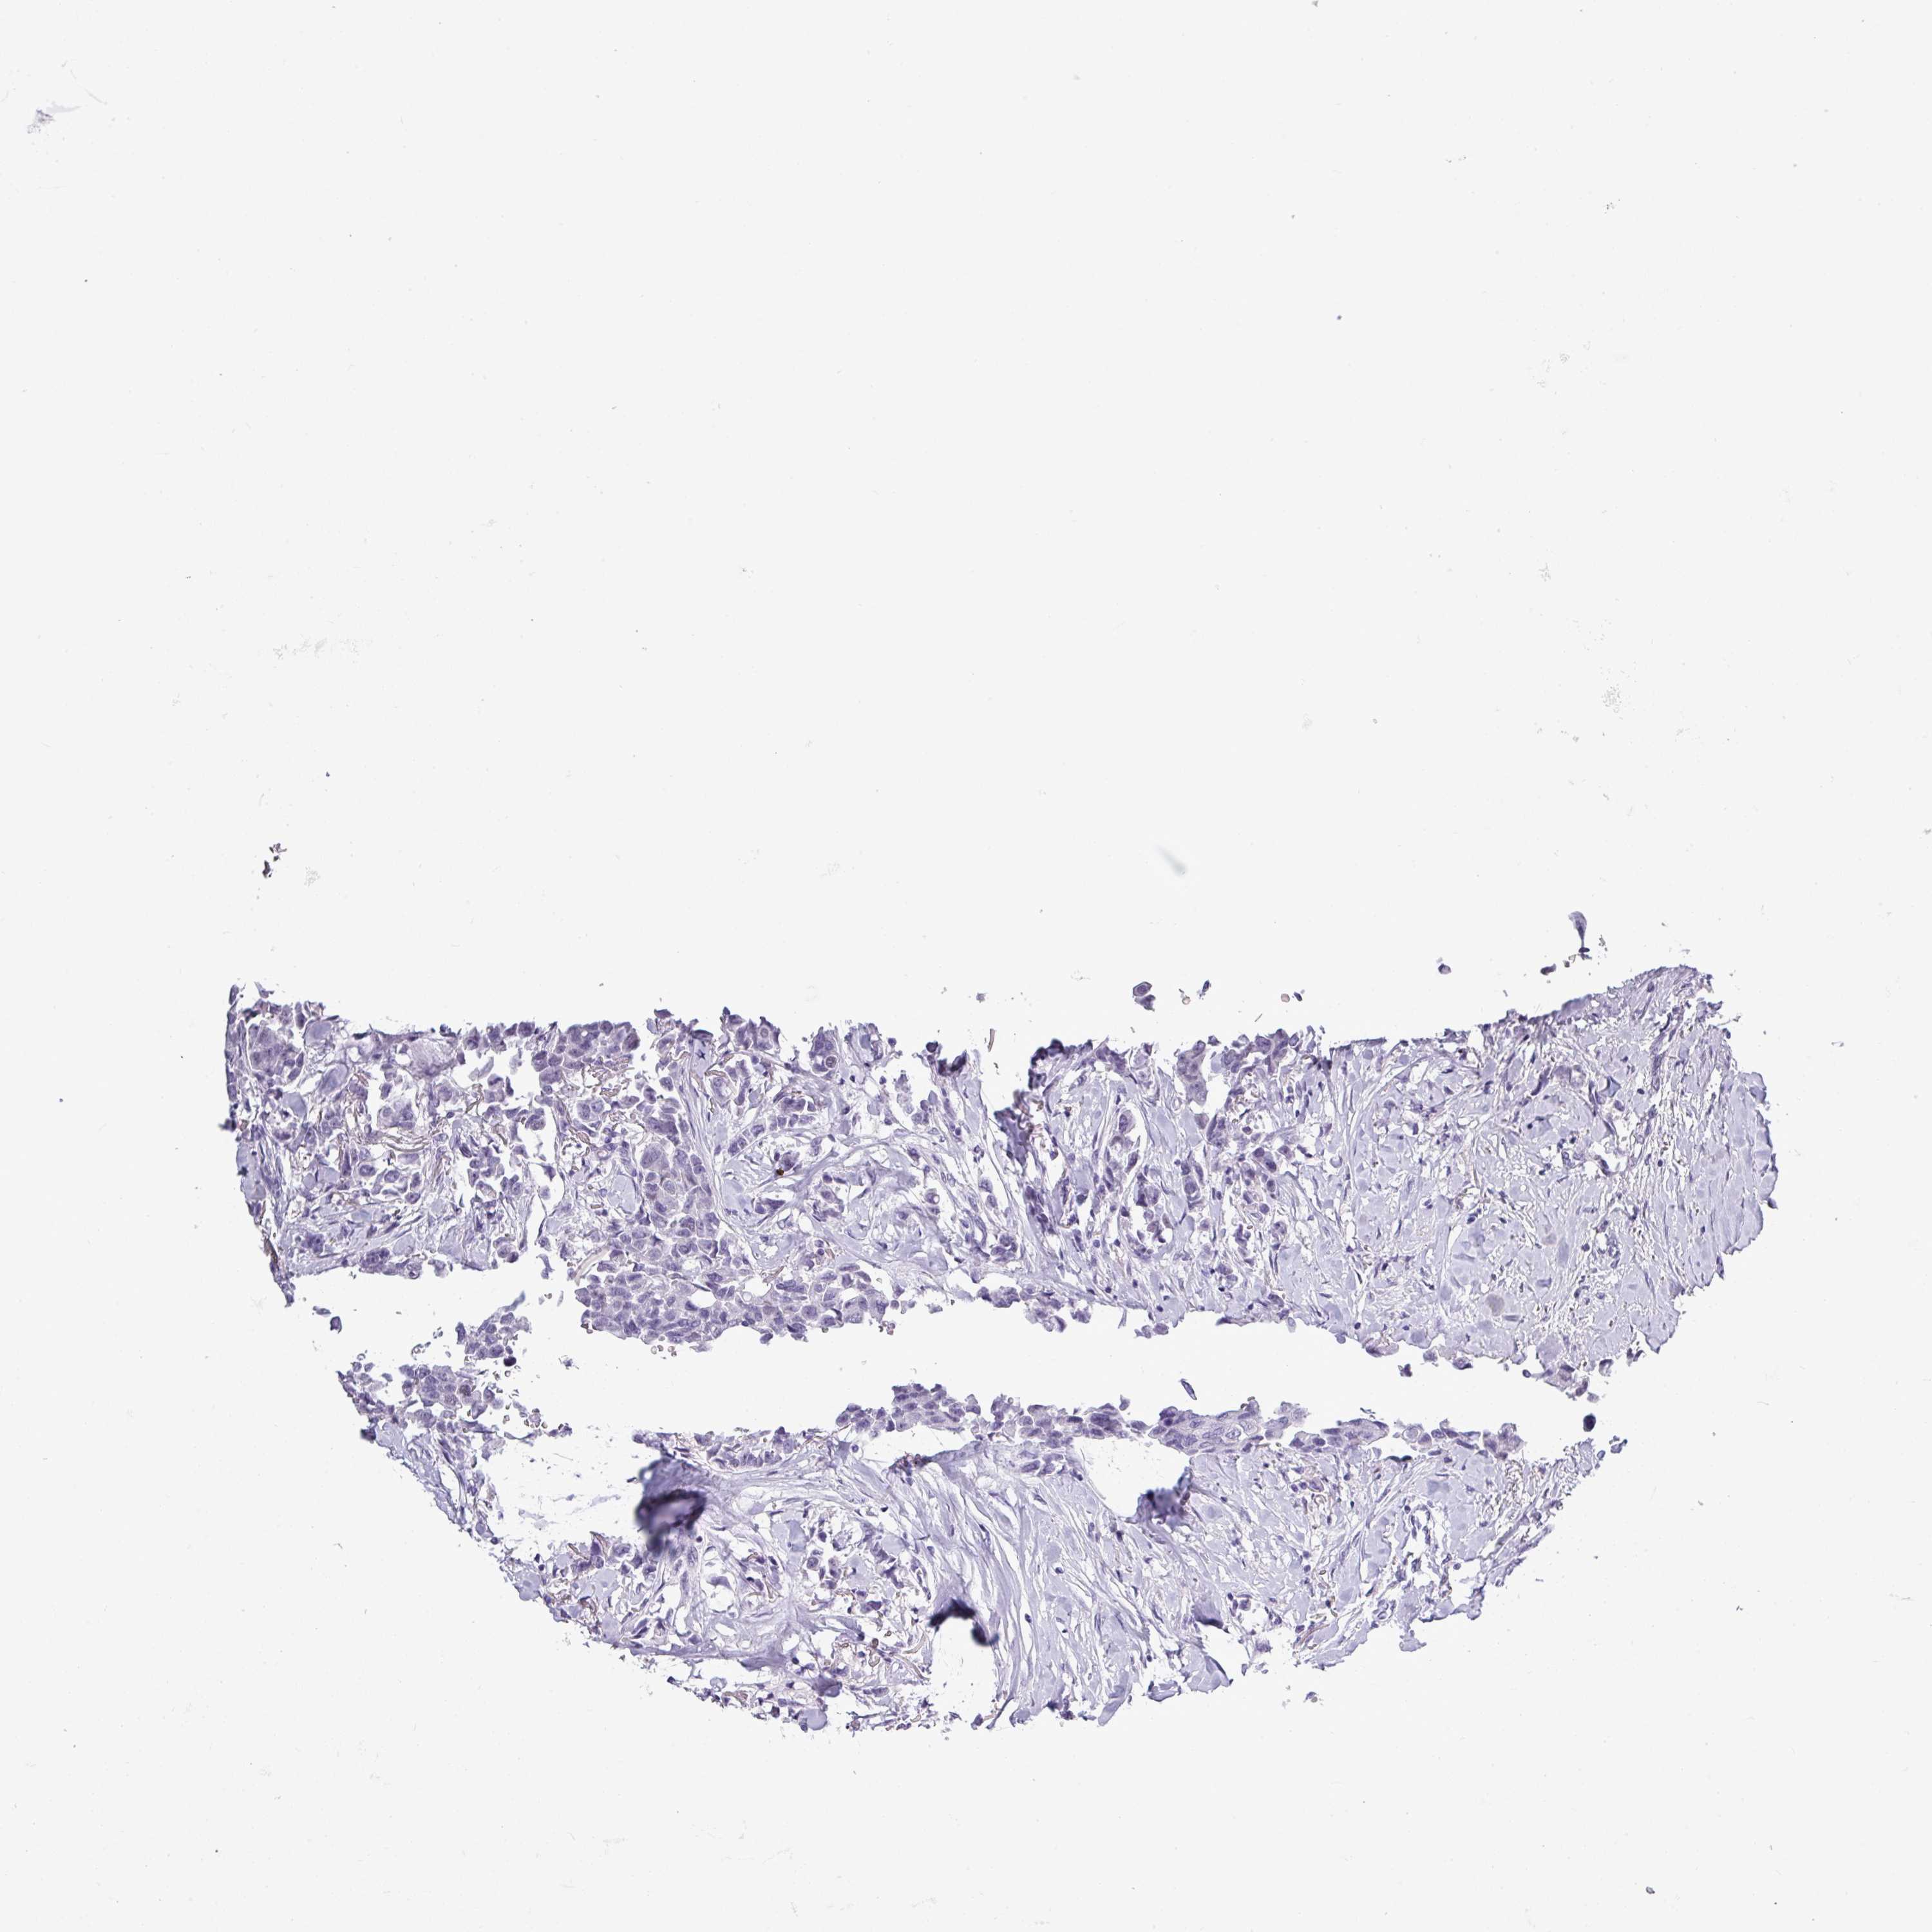

CANCER BREAST CANCER Show tissue menu

BRCA TCGA BRCA VALIDATION PROTEIN EXPRESSION

Breast cancer

Human cancer

Breast invasive carcinoma

SRGAP1 is potential prognostic, high expression is unfavorable in Breast Invasive Carcinoma (TCGA)